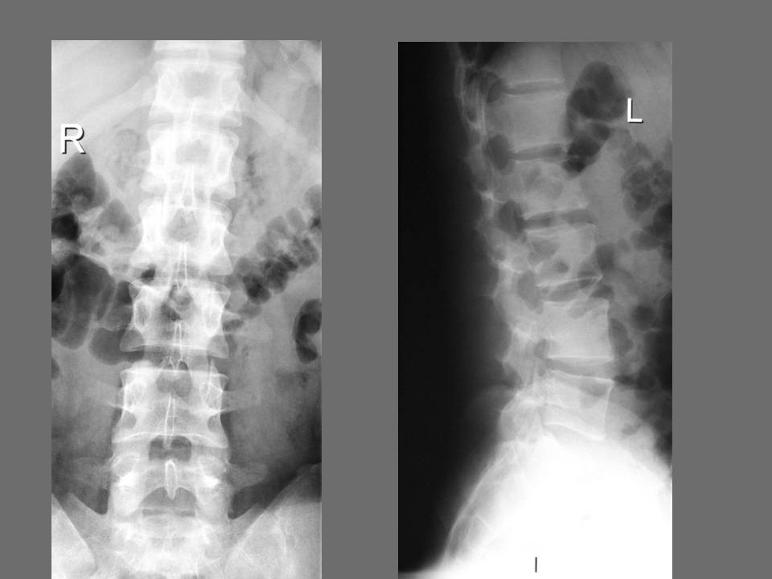

Or "degenerative disc disorder," is a pathologic process of uncertain etiology that may cause acute or chronic low back pain. The typical radiographic findings in DDD are disc space narrowing, vacuum Low back pain. Coccydynia; Sciatica; Radiculopathy; Intervertebral disc disorder ... Read Article

CLINICAL DIAGNOSIS OF LUMBAR DISCOGENIC PAIN Dr Mark Laslett, FNZCP, PhD, Dip.MT, Dip.MDT Registered Physiotherapy Specialist (Musculoskeletal) • Present in 30% of severe acute back pain cases (Hyodo et al) HIZ: High Intensity Zone. 26/08/2014 17 ... Get Doc

Topical Review Discogenic pain - Sld.cu